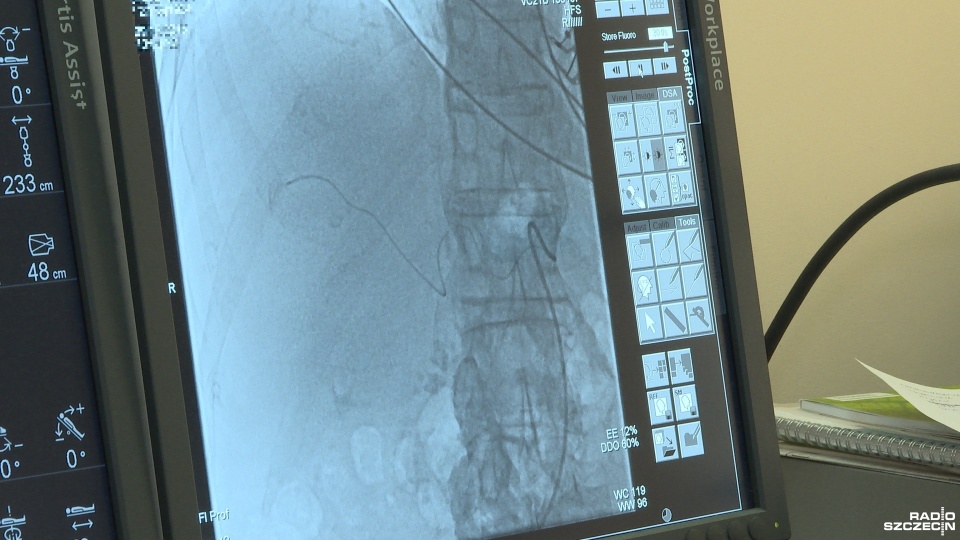

Lekarze podają chemię przez cewnik prosto w zmienione nowotworem komórki. To przynosi lepszy efekt terapeutyczny, pozwala wydłużyć życie pacjentów o kilka lat - mówi prof. Aleksander Falkowski z Zakładu Radiologii Szpitala na Pomorzanach.

- Możemy każdą zmianę nowotworową nasycić tym lekiem, nawet jeśli jest ich kilka w wątrobie. Leczyć każdą pojedynczą zmianę - wyjaśnia Falkowski.